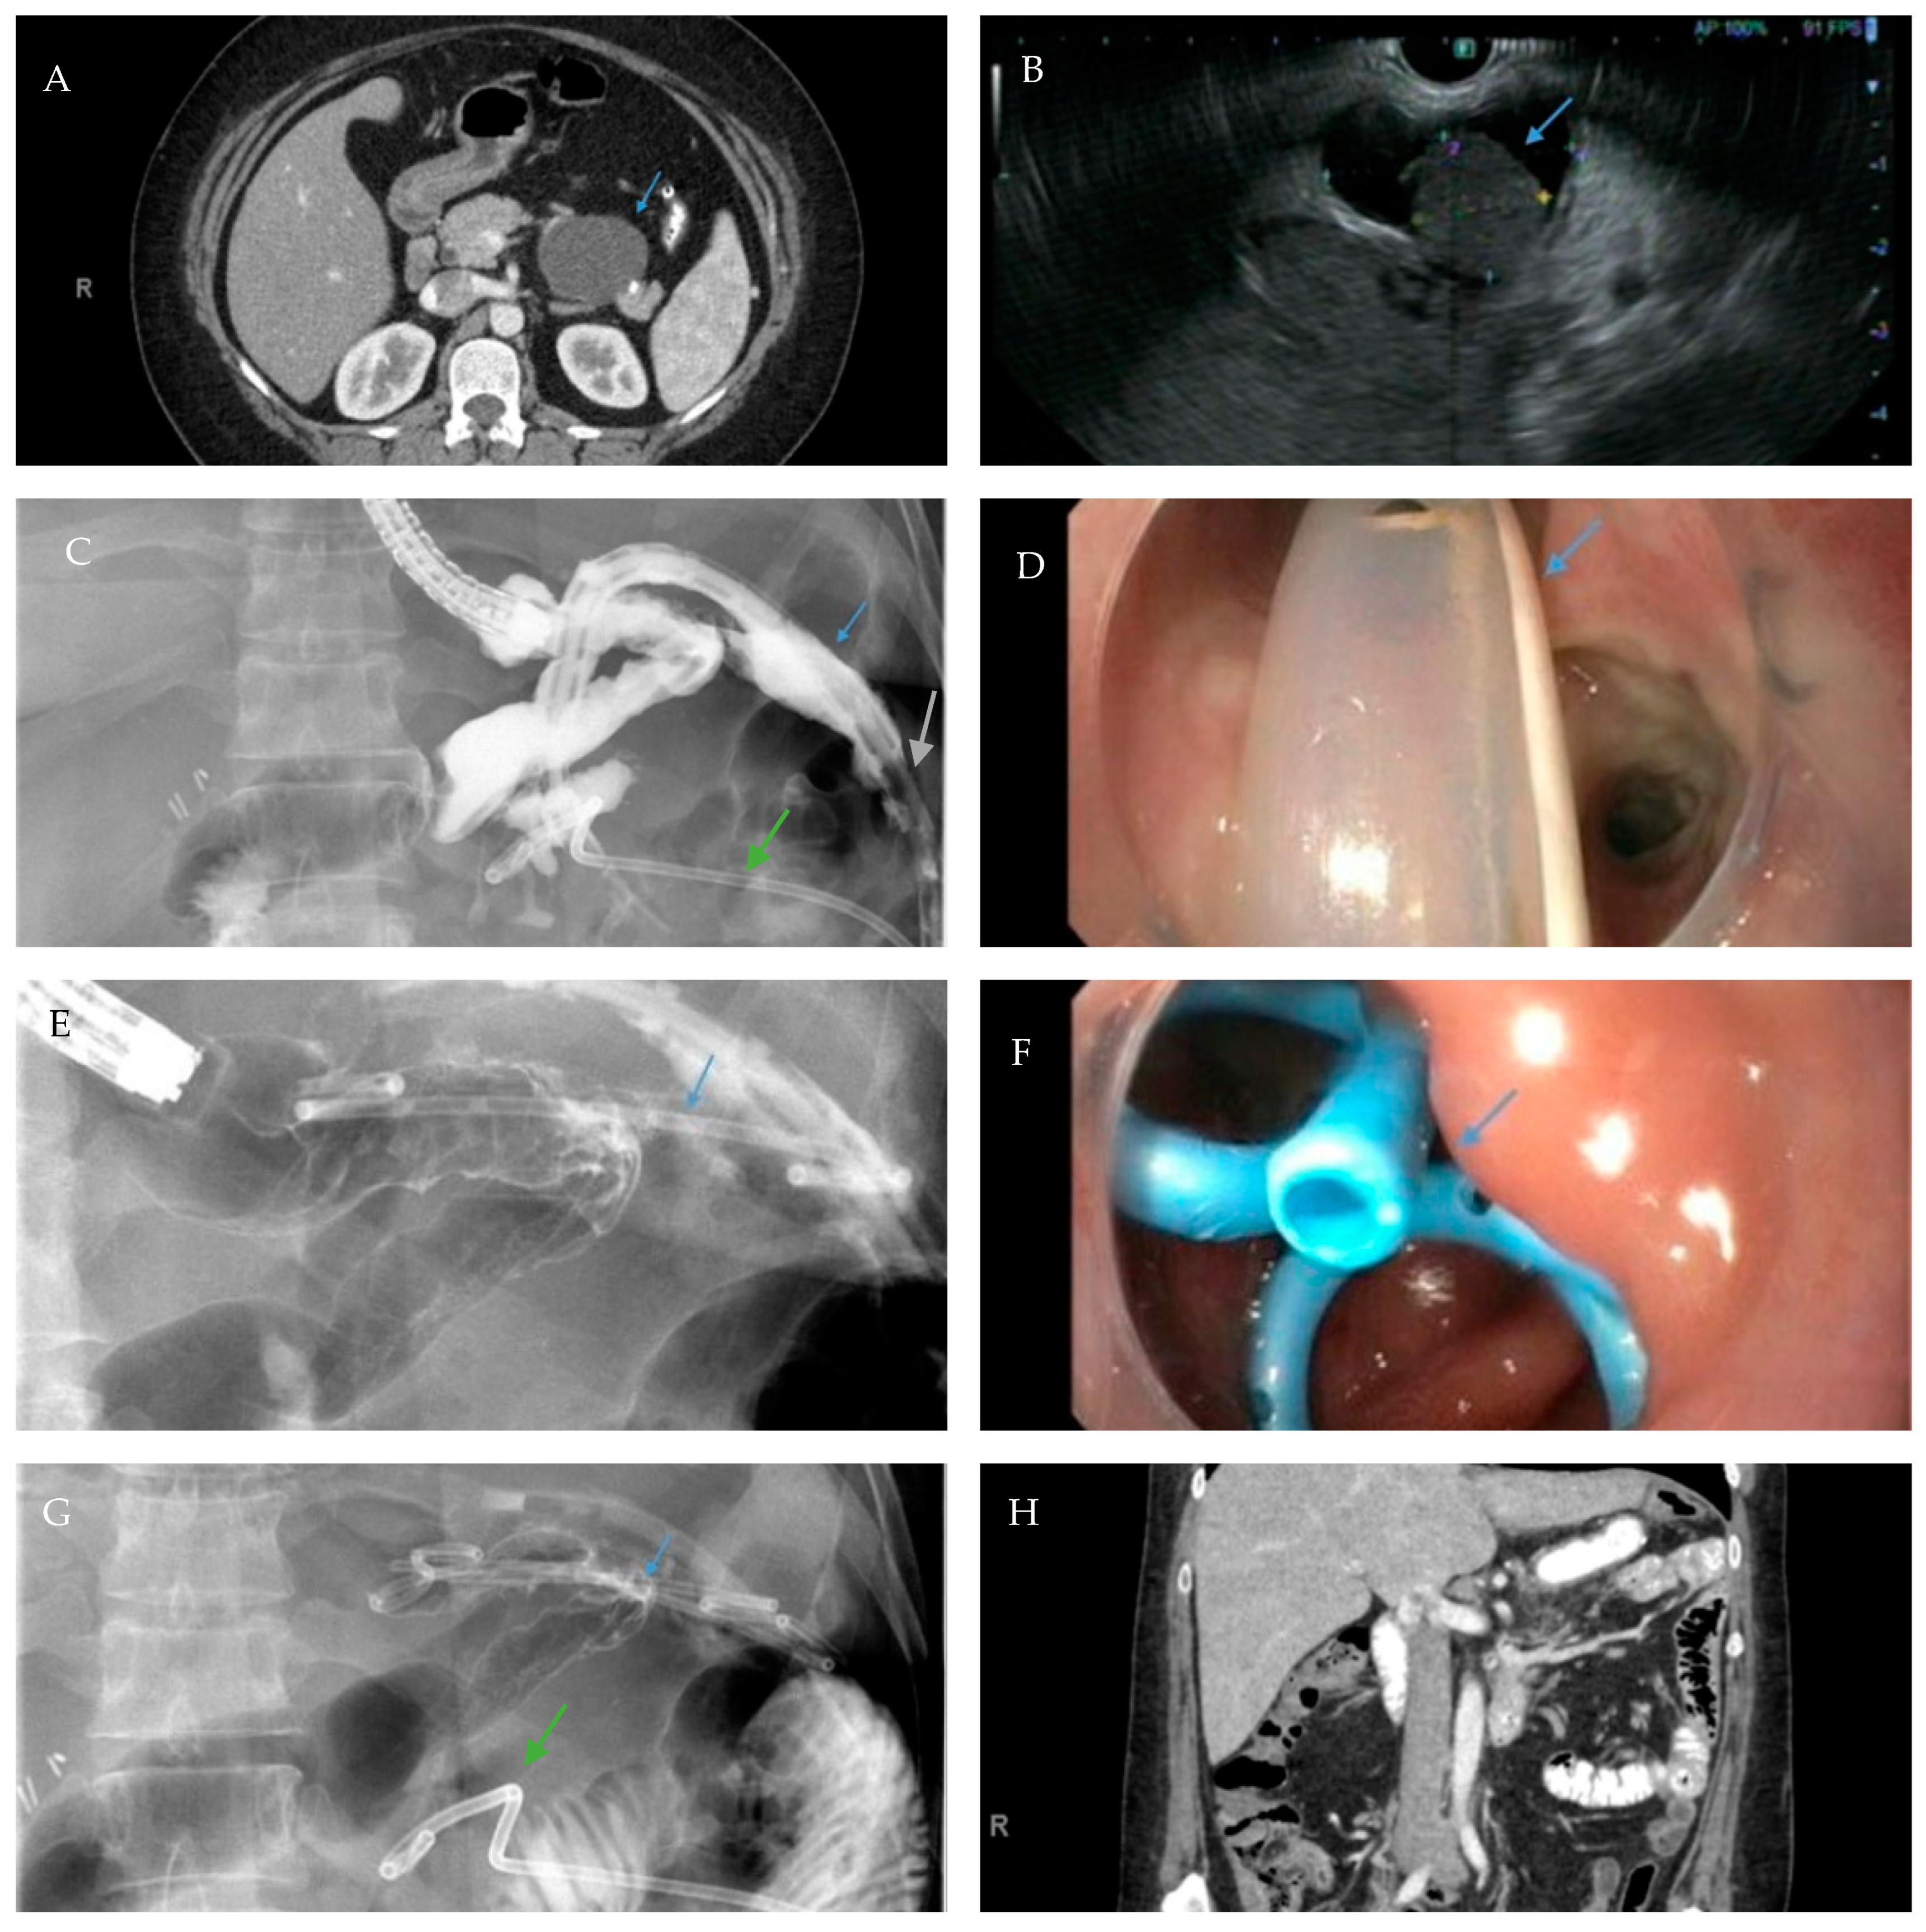

Fluoroscopic image demonstrates the placement of a 23 mm × 15 cm partially-covered esophageal self-expanding metal stent from the distal esophagus to the pylorus (arrow, top left) for the treatment of a leak in a patient following sleeve gastrectomy. Contrast injected endoscopically (arrows, top right and middle left) reveals a small, persistent sleeve leak. The endoscopic removal of the stent was subsequently attempted using a grasper (arrows, middle right and bottom left), but the stent removal was unsuccessful due to tissue ingrowth. A 23 mm × 15 cm, fully-covered, esophageal self-expanding metal stent was placed within the prior stent (arrow, bottom right) to facilitate removal after pressure necrosis of the ingrown tissue.

Axial view of a computed tomography scan of the abdomen and pelvis with contrast reveals a uniform, thin-walled, cystic lesion of the pancreas, which measures 90 mm × 52 mm × 48 mm, with peripheral calcifications with a BMI of 38 (arrow, A). Endoscopic ultrasound demonstrates an anechoic and hypoechoic lesion of the pancreatic body with two compartments, no septae or internal debris, and an associated mural nodule which was suggestive of a mucinous cystic neoplasm (arrow, B). The patient subsequently underwent a laparoscopic sleeve gastrectomy and a concurrent, open distal pancreatectomy which was complicated by a persistent pancreatic leak as well as a gastric sleeve leak (blue arrow, C) as demonstrated by contrast injected through a percutaneous drain (silver arrow, C). The percutaneous drain is redemonstrated on upper endoscopy (arrow, D). Note the additional percutaneous drain in the pancreatic bed for the postoperative leak (green arrows, C,G). Endoscopic internal drainage using transgastric double-pigtail stents was performed as demonstrated on fluoroscopic imaging (arrows, E,G) and endoscopy (arrow, F). After a prolonged course, the patient had a complete recovery, and a follow-up CT scan of the abdomen and pelvis confirmed the resolution of the leak and the removal of the double-pigtail stents and percutaneous drains (H).

Gastric sleeve stenosis in the patient depicted in Scheme 5 was treated with through-the-scope balloon dilation to 20 mm as demonstrated on fluoroscopic image (arrow, left) and upper endoscopy (arrow, middle). Endoscopic contrast injection following dilation revealed improvement in the stenosis and flow of contrast (arrow, right). Note a small residual drain (green arrow, left).

Contrast injected endoscopically reveals a sharp angulation and stenosis of the sleeve in a patient following sleeve gastrectomy (blue arrow, left and top right). A pneumatic balloon dilation (green arrow, top right) was performed to 35 mm. Endoscopic contrast injection reveals no post-dilation leak of contrast (bottom right).